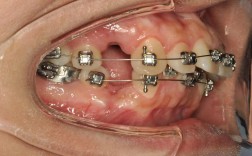

固定矫治(如传统金属托槽矫正、陶瓷托槽矫正)通过施加持续矫治力,移动牙齿调整咬合,对于牙性反颌,可通过“摇椅弓”“颌间牵引”等方式将上前牙唇向移动、下前牙舌向移动;对于轻度骨性反颌,可通过拔牙为牙齿移动提供空间,图片中,固定矫治治疗前后对比可见,原本“下包上”的牙齿关系变为正常覆颌覆盖,牙列排列整齐(图2:固定矫治前后口内照,治疗前下前牙位于上前唇侧,治疗后上下前牙正常对刃)。